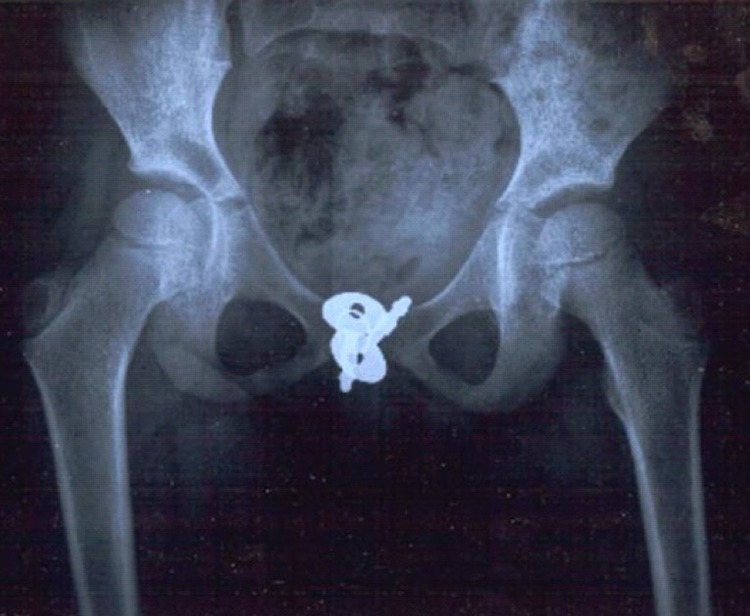

Awalnya, doktor menjalankan ujian air kencing dan juga imbasan (ultrasound) di bahagian abdomen bawah, namun semuanya menunjukkan keputusan normal tanpa sebarang kelainan. Kemudian, doktor beralih kepada prosedur MRI dan juga X-ray pada bahagian pelvis. Di sinilah segalanya terjawab, mereka menemukan objek berupa logam di bahagian ‘Miss V’ yang merupakan kunci buku diari.